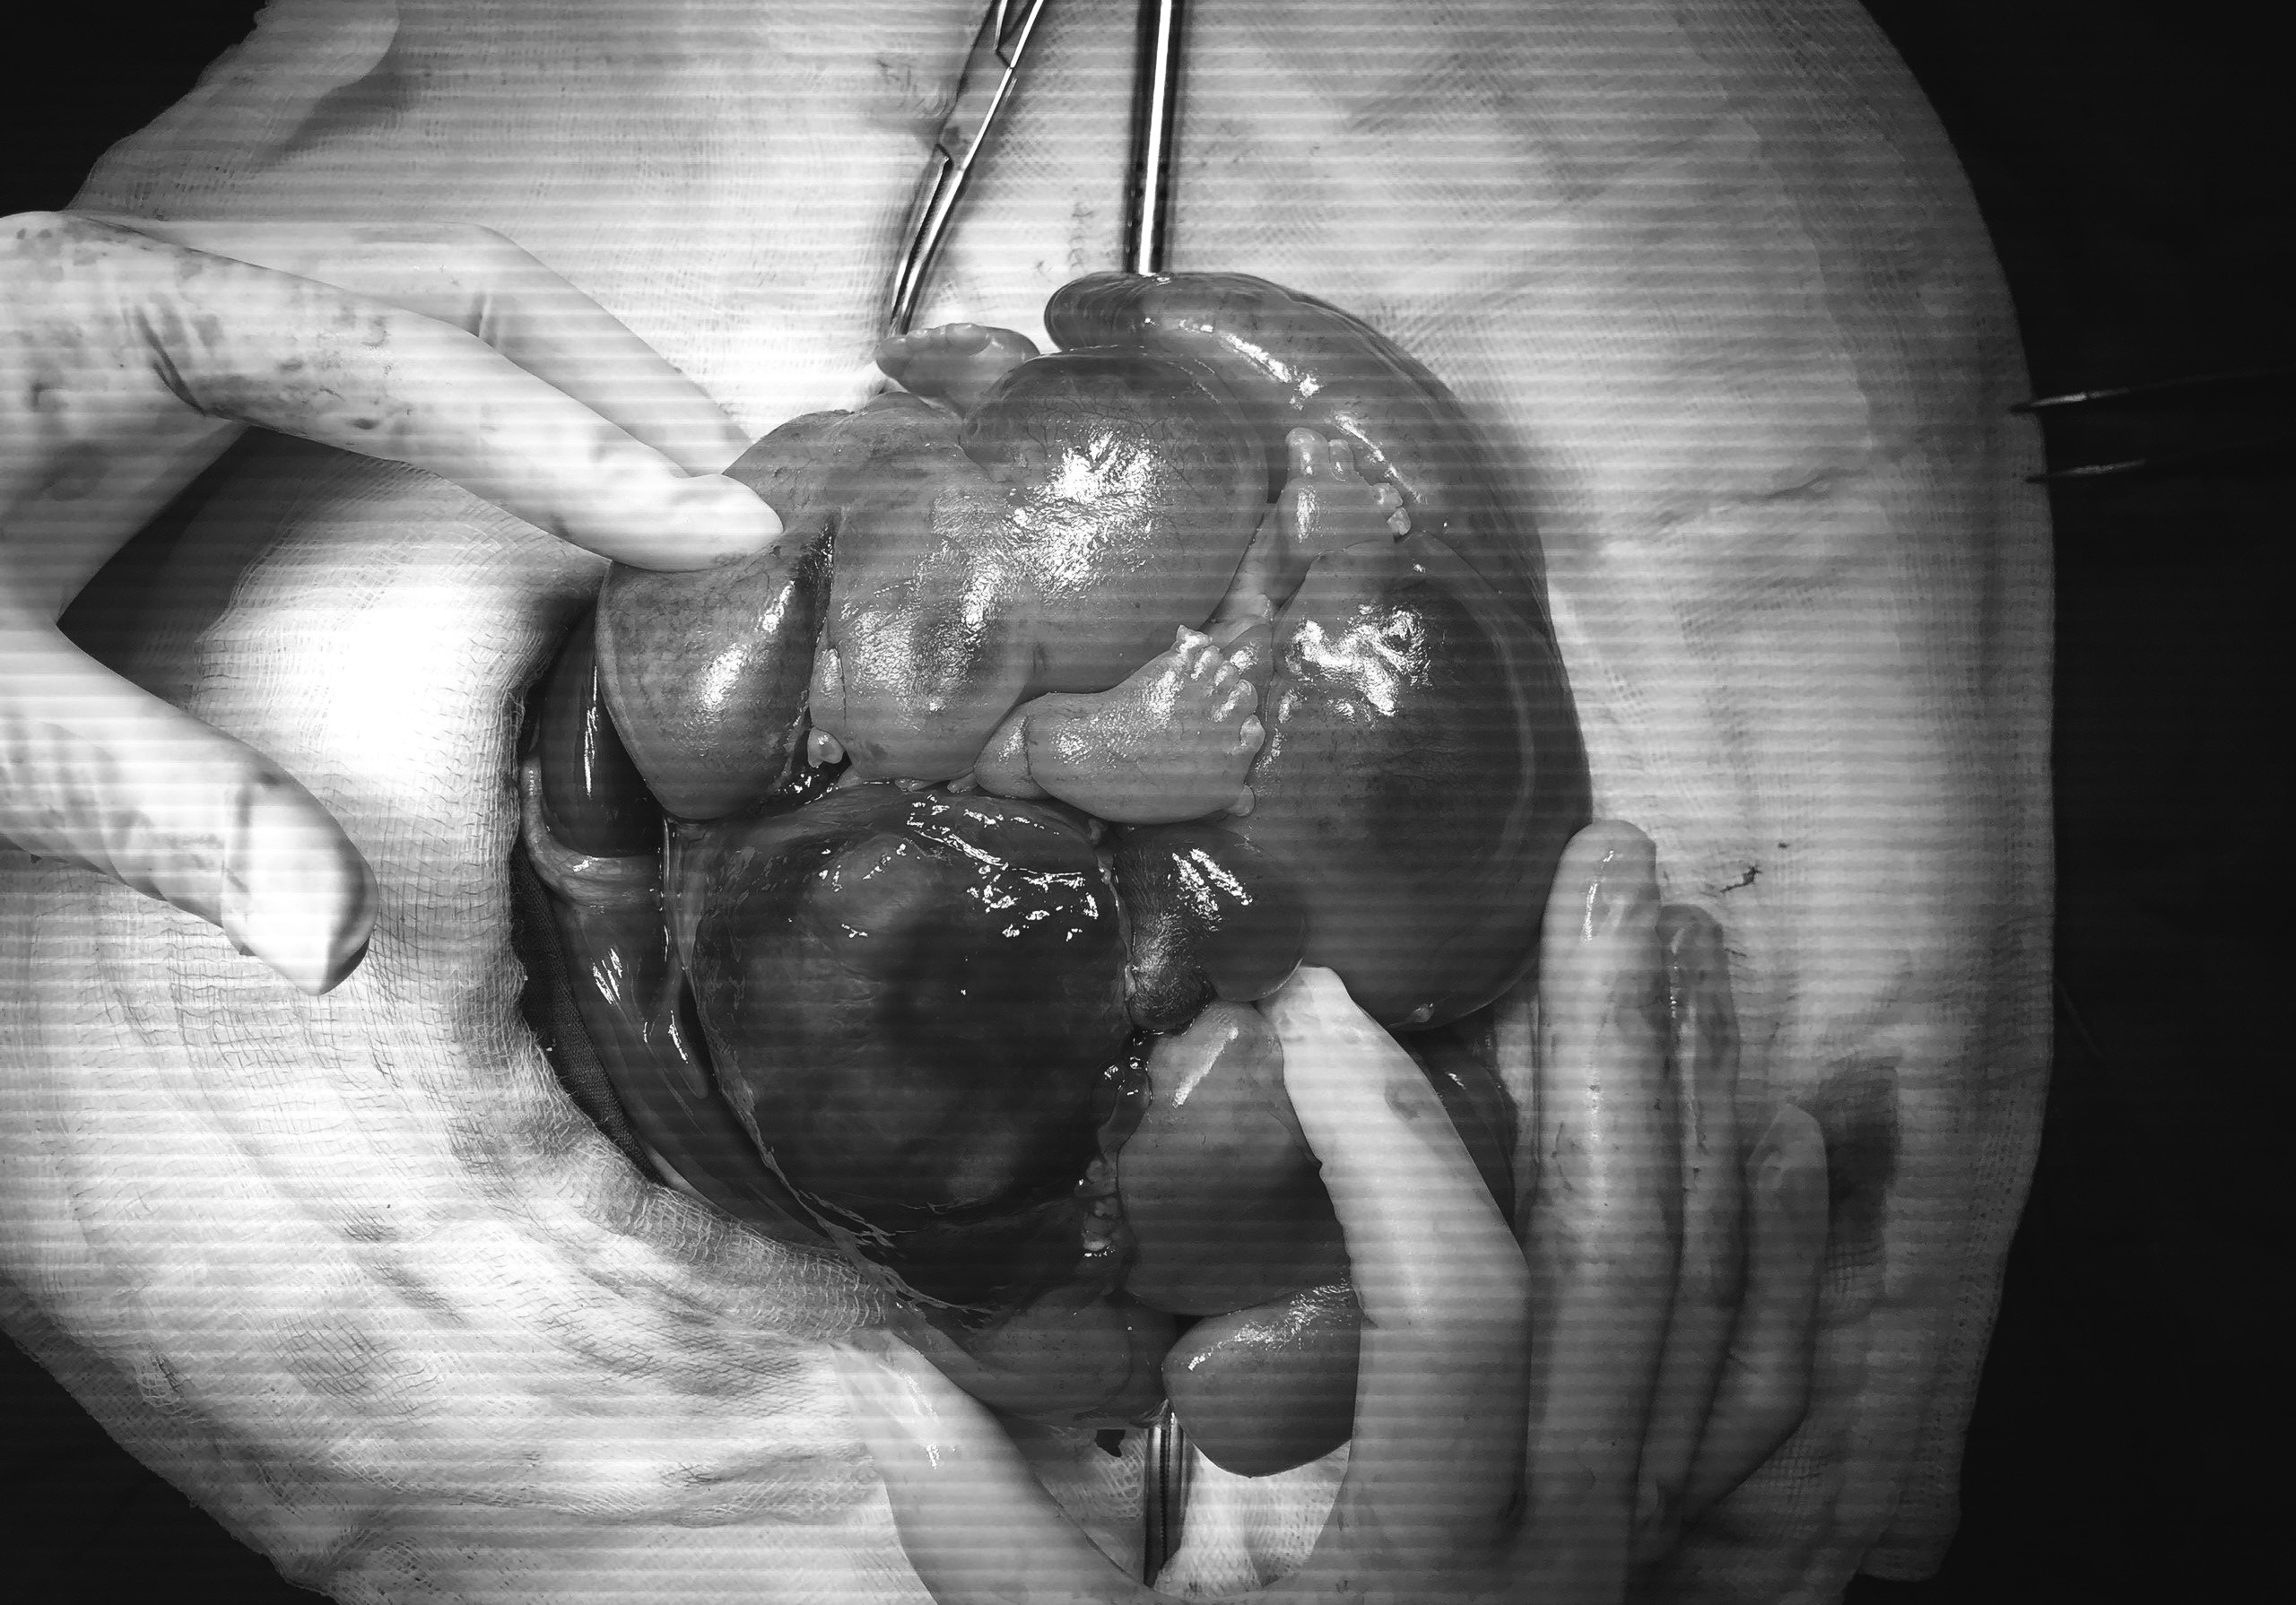

Bé gái sơ sinh mang khối u gần giống thai nhi trong bụng. Ảnh: Thúy Nguyễn.

Trong lúc phẫu thuật, các bác sĩ ghi nhận khối u có dạng bào thai. Túi chứa dịch nằm cạnh khối này tương tự túi ối, cùng với nhiều cấu trúc như xương vai, xương ống, xương cột sống không hoàn chỉnh, tuy nhiên, hình dạng các chi trưởng thành khá rõ.

Sau hơn một giờ phẫu thuật, các bác sĩ loại bỏ thành công khối u trong bụng bé sơ sinh. Tình trạng hô hấp của bé được cải thiện rõ rệt.